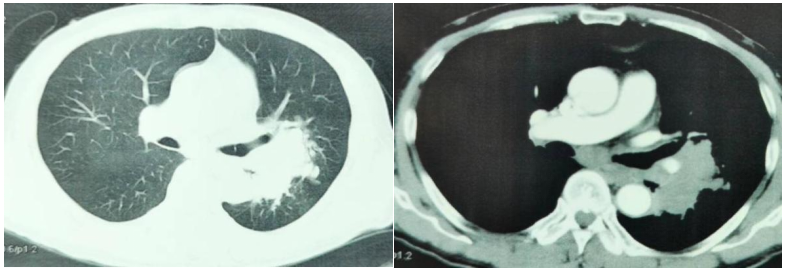

胸部增强CT(2022-05-17):考虑肿瘤性病变伴阻塞性炎症(左肺下叶背段支气管阻塞,肺门处见软组织团块影,呈分叶状,大小约9.8cm×4.6cm,包绕邻近血管);肿块旁多发小结节,子灶?左肺门及纵隔多发转移瘤。

图1.胸部增强CT

电子支气管镜检(2022-05-17):可见左主支气管粘膜充血,管腔变形,略显狭窄;左上尖段支气管粘膜肿胀,左下背段支气管被菜花样肿物完全阻塞。

复查增强CT(2022-06-29):1.左肺上下叶见不规则形团块影(8.45cm×5.7cm);考虑肿瘤性病变伴阻塞性炎症;肿块旁多发小结节,子灶?左肺门及纵隔多发转移瘤。2.肝脏多发低密度结节影,较大者直径约1.1cm,增强不均匀强化。3.左侧肾上腺结节状增粗、不均匀强化,转移瘤可能。4.左肺下叶点状钙化灶。

第1周期治疗后疗效评估结果:SD。